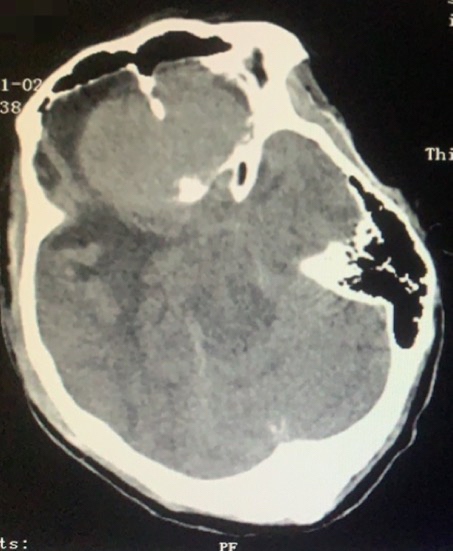

病例二:女,66岁,发现颅内占位5年,意识不清5天坐轮椅来诊。既往史无特殊。

术前CT